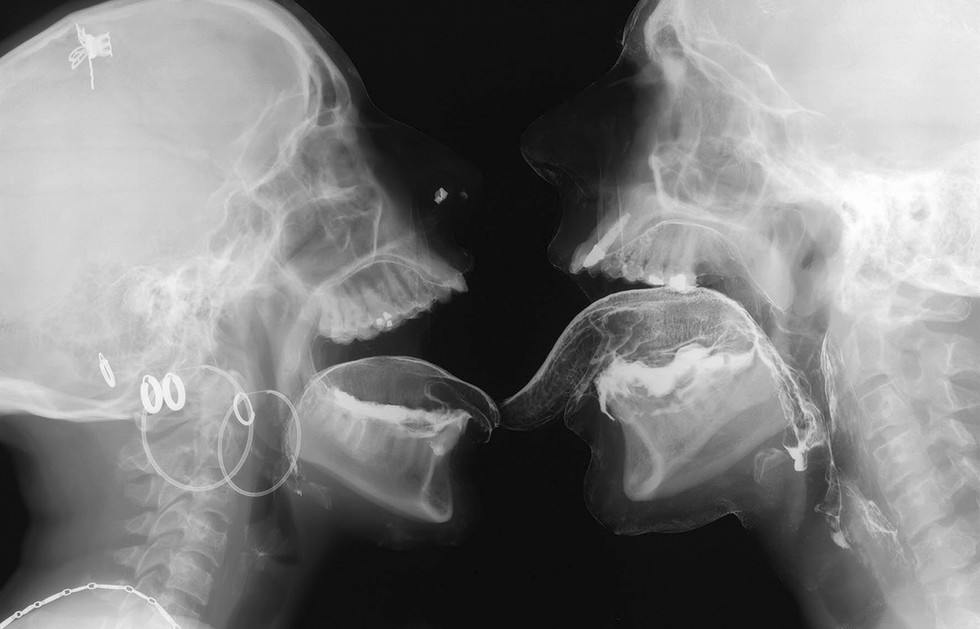

Beginning around 2001, Delvoye initiated Sexrays, a project that involved his first major foray into contemporary radiological imagery. Working with a cooperating radiologist, he arranged for a group of friends to participate in X‑ray sessions inside medical imaging facilities. The participants applied small quantities of barium, commonly used as a contrast agent in radiology, to make certain parts of the body visible during scanning. They then performed intimate physical interactions while being recorded by X‑ray machines. Delvoye observed the process remotely on a computer monitor in another room, allowing the participants enough distance and privacy to behave naturally.

For the stained glass window works, Delvoye used X‑ray images taken during intimate encounters between two friends. The skeletal images produced by the radiographs were incorporated directly into stained-glass compositions and placed within Gothic-style window frames. From a distance the windows appear abstract, their luminous shapes resembling decorative patterns of light and color. Only when viewed closely do the anatomical elements emerge: skulls, teeth, spinal columns, and ribs forming intricate visual arrangements. In some panels the figures are clearly interacting, even kissing.

The imagery itself consists primarily of thousands of individual radiographic frames depicting skeletal structures, spinal columns, skulls, teeth, lungs, and various bodily gestures. In place of saints or biblical scenes, Delvoye created panels so that they would depict skeletal figures embracing, kissing, and interacting within the architectural frameworks of typical Gothic church windows. Yet the images reveal very little of the emotional dimension of human intimacy. Instead, the bodies appear as mechanical structures, bones and joints moving through space, suggesting that radiography reduces the human body to a kind of biological machine.

Delvoye himself has framed the work through a deliberately materialist perspective. “I only believe in what I can see. In my universe there is no soul and there is no love. I’ve never seen the soul and I’ve never seen love. I’ve seen skeletons, teeth, penises, lungs with X‑rays. I’ve never seen love.” The statement captures the conceptual tension underlying the project: the contrast between the invisible emotional meanings normally associated with human relationships and the stark physical evidence produced by medical technology. Despite the nihilistic impression it may convey at first, the works are meant to truly elicit a sense of contemplation.

Within this context the images function almost like contemporary vanitas compositions. In the tradition of seventeenth-century European art, vanitas imagery often used skulls and skeletal motifs to remind viewers of mortality. Delvoye’s X‑rays similarly confront the viewer with skeletal forms that appear simultaneously ghostlike and mechanical. Rather than revealing hidden emotions, the radiographs emphasize the connection between physical desire and mortality, linking sex and death within a single visual structure.

In this sense the X‑ray windows are less about eroticism than about exposing the mechanisms through which society constructs meaning around the body. By placing skeletal imagery inside structures associated with sacred art, Delvoye shortens the distance between devotion, mortality, and physical existence, reframing the cathedral window as a site where biology, technology, and symbolism intersect.